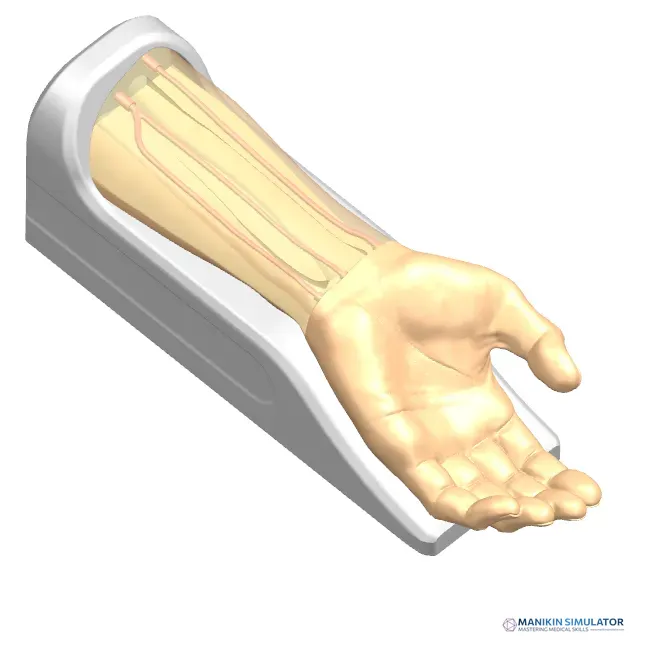

Radial Artery Puncture Operation Model (Ultrasound Guided) adalah simulator lengan bawah untuk pelatihan kanulasi arteri radialis dengan panduan USG. Arteri radialis dibuat berdasarkan data CT manusia.

Material komposit khusus memungkinkan visualisasi arteri yang jelas di layar USG *real-time*. Memberikan sensasi ‘tembus’ (*breakthrough*) yang realistis saat jarum menembus dinding arteri.

Drawing of Radial Artery Puncture Operation Model (Ultrasound-Guided)